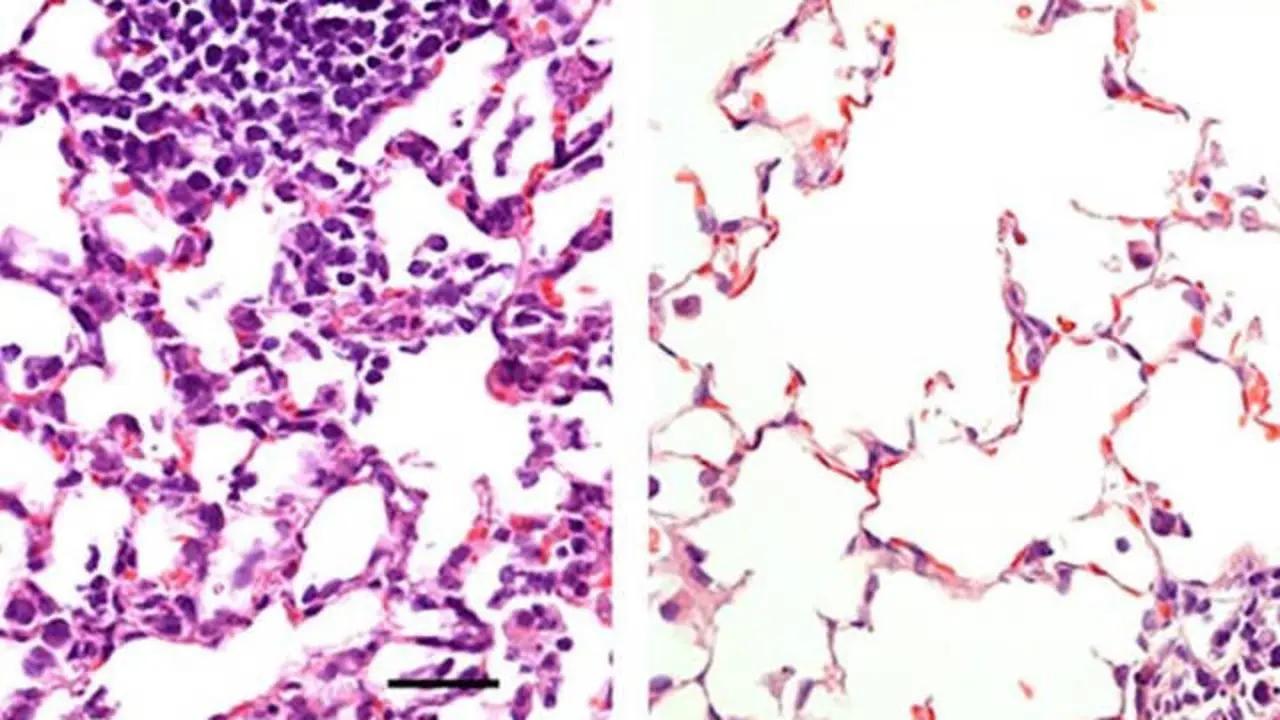

Una vacuna nasal contra el Covid-19 previene la infección en los ratones Científicos de la Facultad de Medicina de la Universidad de Washington en San Luis (Estados Unidos) han desarrollado una vacuna que ataca el virus… Europa Press 25/08/20